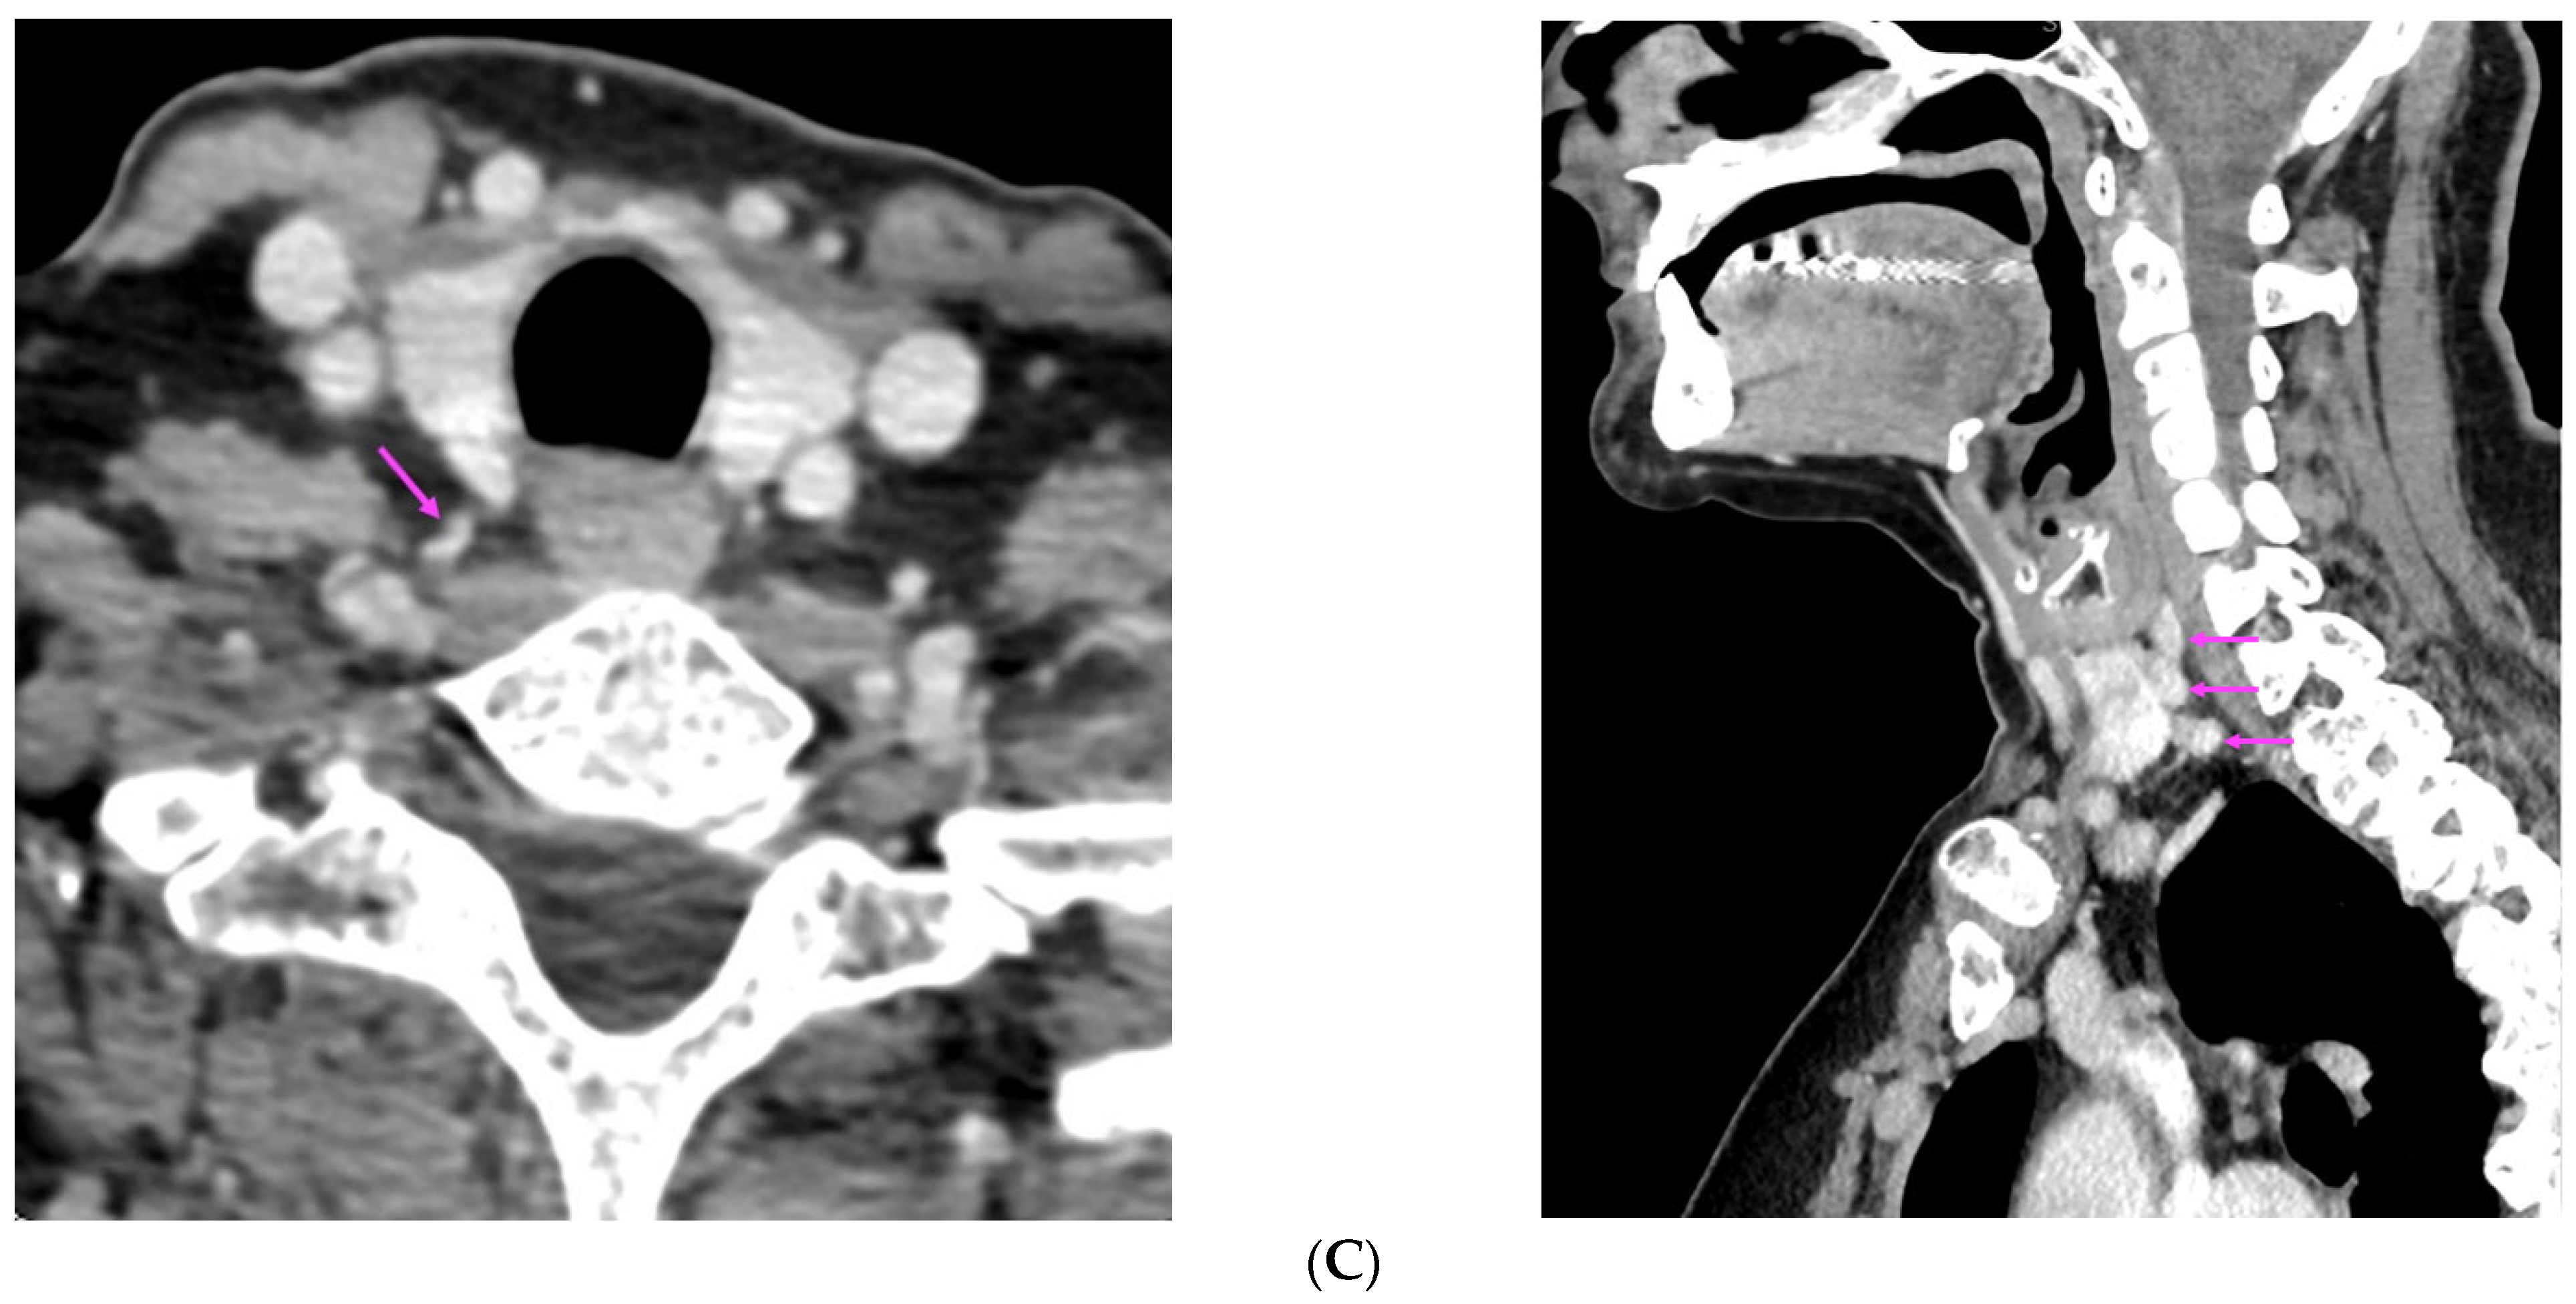

| [30] | US: two hypoechoic nodules posterior to left thyroid lobe SPECT/CT: no tracer uptake in neck, mediastinal nodule | Diffuse nodular hyperplasia and hyperplasia around suture material (cervical nodules) Nodular hyperplasia of parathyroid tissue (mediastinal nodule) |

| [37] | US: six nodules of 5 mm to 16 mm located subcutaneously anterior of right sternocleidomastoid muscle 99m-Tc sestamibi scintigraphy: no hyper-functional foci CT: similar to US | Parathyromatosis |